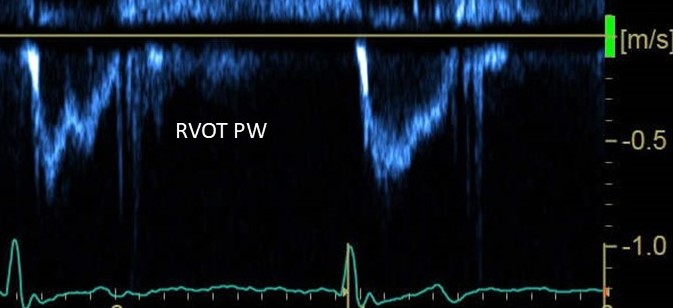

DILV Apical view demonstrates - two AV valves aligned & empty into a dilated left ventricle with fine apical trabeculations. American Society of Echocardiography Ritu Thamman MD Alex Felix Rohit loomba Deepak Thekkoott #am-writing MD Chittur Sivaram Alexander Mladenow MD NeoCardioLab - Gabriel Altit Sujith Pereira 🇮🇳🇬🇧🏏🚴 Swati Garekar ESC WG on ACHD Chairperson Edgar Argulian American College of Cardiology